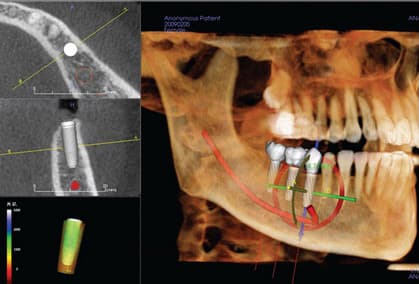

i-CAT + E4D = 3-D Integration At Its Best

What happens when E4D meets i-CAT 3-D? The result is a dynamic pairing of technologies for implant and restorative planning and placement—expanded clinical capabilities, workflow, and time savings at its best! i-CAT technology is already adding more precision to dental planning and treatment. During the implant process, the ability to see a “surgical view” before surgery, or to even avoid surgery altogether, is of great benefit both to the dentist and the patient. The capability to view the image 360 degrees offers the clinician the confidence that he/she will not be confronted with any surprises that impede the achievement of the ultimate goal—the successful placement of the implant. E4D CAD/CAM

CBCT-A Clear Perspective on Implant Options

By Joel L. Rosenlicht, DMD With the growing popularity of implants, many dentists are exploring ways to add this type of procedure to their treatment options. When implants are indicated, the process of determining the optimal treatment plan starts even before the details of the implant itself are considered. The opportunity to view a three-dimensional scan of my patient’s anatomy before starting an implant makes me a better dentist. My i-CAT® provides me with better visualization and a clearer perspective on my options. Most importantly, CBCT gives me the ability to achieve my desired results more easily and less stressfully. Not only do 3-D images prepare the dentist for